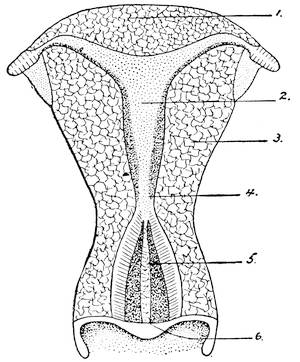

Mons of Venus, labia majora, minora, vestibule, bulbs, clitoris, Bartholinian glands, hymen, vagina, uterus, broad and round ligaments, viiitubes, ovaries, Graafian follicle, ovum.

At the caudal end, the Müllerian ducts fuse together into

one, the walls, along the entire line of the union, degenerate,

and the two ducts thus form a single duct, the later vagina and

uterus. Until the fifth month there is no distinction between25

26

vagina and uterus, the two organs form a single sac-like structure.

At the beginning of the fifth month, a circular ridge in

the wall of the sac makes its appearance and marks the division

between the vagina and the uterus. When the lower portion of

the two Müllerian ducts have fused to form a single canal, the

utero-vaginal sac, the lumen of the vagina is still obliterated,

being filled with epithelial cells. By the breaking down of the

central epithelial cells, the cavity is established.

At this period a little semicircular crescentic fold attached to the dorsal margin of the aperture of the vagina arises and forms the hymen, an organ which has always played such an important rôle in the fancy of all nations.

The upper blind ends of the Müllerian ducts, with their expanded funnel-shaped mouths, diverge and form the oviducts, or the Fallopian tubes.